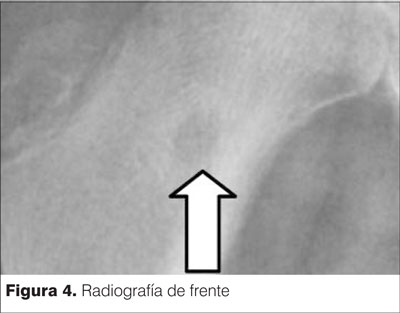

En la radiografía de cadera de frente se observa una imagen lítica redondeada con halo escleroso a nivel de cuello de fémur muy sugestivo de un osteoma osteoide. Imagen conocida como signo de la escarapela (figuras 3 y 4).